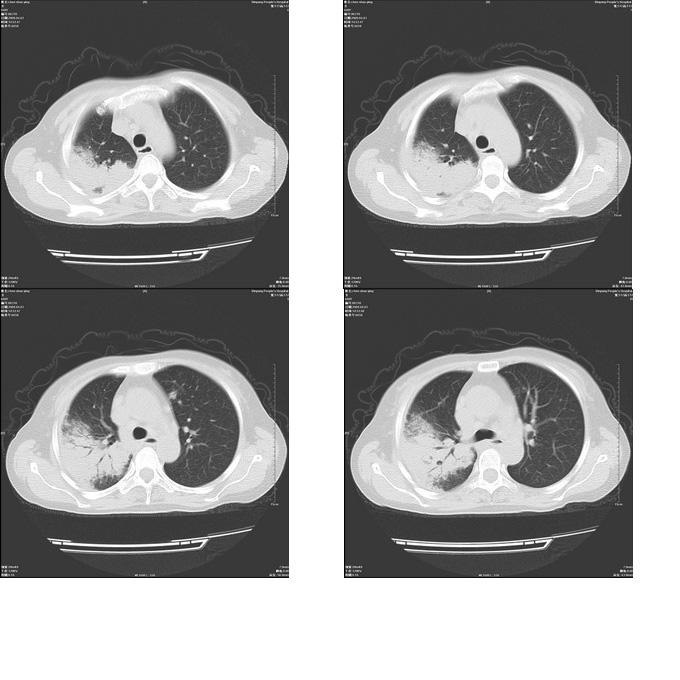

患者,女,48岁,发热伴陈发性咳嗽5天,偶尔痰中带血。体温约38°~40°;白细胞明显减低0.85x10的9次方/升。入院后抗炎、抗痨一周复查病灶明显进展。

右上肺后段实变影,内见支气管气象,肺门未见软组织肿块,气管前方有肿大淋巴结。左下肺见多个类圆形结节影。考虑:1.右上肺后段大叶性肺炎,需进一步检查病原体种类,应多询问病史,条件许可考虑做纤支镜检查2.左下肺结节影性质待定

问题是抗炎治疗一个星期后病灶进展。

右肺片状实变影,左肺结节影,抗炎及抗捞治疗后病灶进展。

我考虑:不能除外肺炎型肺泡癌可能。建议查痰或活检。